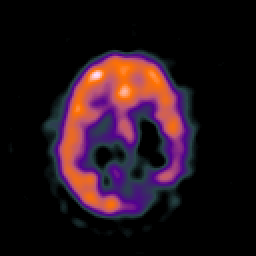

SPECT TC Study #8 -- Slice #36

[Home][Help][Clinical][Tour 1][Tour 2][Tour 3] Slice 36